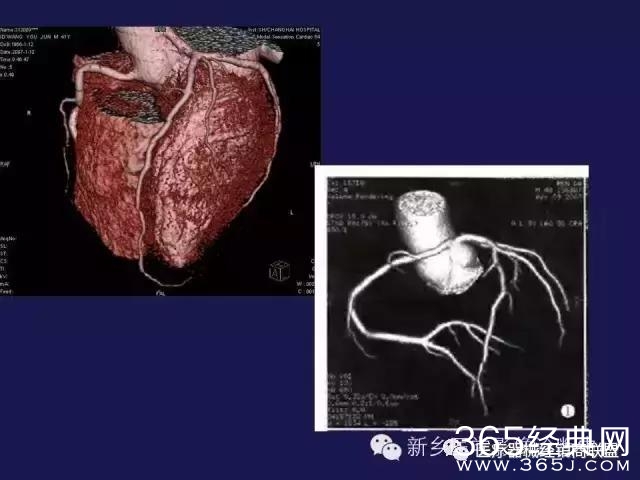

CT、MRI很难?NO,今日我们一起来学习一下如何读CT、MRI!

内行看门道:

整整90张图

强烈建议大家收藏后再观看